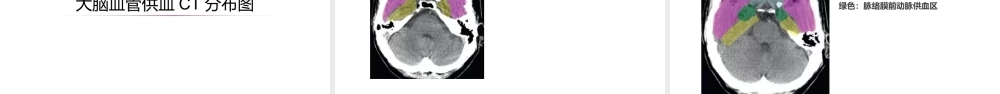

神经系统(二)脑动脉血管脑的动脉脑动脉的两个系统来源1、颈内动脉系(前循环)2、椎-基底动脉系(后循环)3、大脑动脉环(连接)颈内动脉系端脑前2/3间脑的前部椎基底动脉系端脑后1/3间脑后部脑干、小脑颈内动脉系颈内动脉系颈内动脉:发自颈总动脉,经破裂孔入颅。主要分支:脉络膜前动脉后交通动脉大脑前动脉大脑中动脉颈内动脉大脑前动脉--供应大脑半球内侧面发自颈内动脉,沿胼胝体沟直达胼胝体压部的后方,与大脑后动脉末稍吻合。大脑前动脉大脑后动脉大脑中动脉--供应大脑半球背外侧面发自颈内动脉,进入大脑外侧沟,在岛叶与颞叶之间斜向后上。大脑中动脉椎-基底动脉系椎动脉(发自锁骨下动脉,经枕骨大孔入颅后,左右椎动脉渐靠近,多在脑桥下缘会合成基底动脉。)1、小脑后下动脉2、脊髓前、后动脉基底动脉(行至脑桥上缘,分成左右大脑后动脉两大终末支。)1、小脑上动脉2、小脑前下动脉3、脑桥动脉4、迷路动脉5、大脑后动脉基底动脉椎动脉大脑后动脉(基底动脉的终末支)供血区:枕叶底面、颞叶内侧面为主。大脑后动脉大脑动脉环(Willis环)颈内动脉系和椎-基底动脉系吻合形成封闭的七边形血管环。意义:是一种代偿的潜在装置。缺血性脑血管疾病时,侧枝循环最充分的供血来源。大脑中动脉大脑前动脉后交通动脉前交通动脉椎动脉基底动脉颈内动脉颈外动脉颈总动脉锁骨下动脉头臂干海绵窦岩部海绵窦+岩部=“虹吸部”组成前交通动脉双侧大脑前动脉颈内动脉分叉部双侧后交通动脉(变体;连接大脑后动脉,吻合并入威利环:动脉瘤的多发区域)双侧大脑后动脉基底动脉顶端变体存在多种胚胎原始特征大脑血管供血CT分布图浅蓝色:大脑前动脉终末支供血区粉红色:大脑中动脉终末支供血区黄色:大脑后动脉终末支供血区浅蓝色:大脑前动脉终末支供血区粉红色:大脑中动脉终末支供血区黄色:大脑后动脉终末支供血区绿色:脉络膜前动脉供血区浅蓝色:大脑前动脉终末支供血区粉红色:大脑中动脉终末支供血区黄色:大脑后动脉终末支供血区绿色:脉络膜前动脉供血区褐色:大脑前动脉深穿支供血区枣红色:大脑后动脉深穿支及后交通动脉供血区浅蓝色:大脑前动脉终末支供血区粉红色:大脑中动脉终末支供血区黄色:大脑后动脉终末支供血区绿色:脉络膜前动脉供血区褐色:大脑前动脉深穿支供血区枣红色:大脑后动脉深穿支及后交通动脉供血区亮红色:大脑中动脉深穿支供血浅蓝色:大脑前动脉终末支供血区粉红色:大脑中动脉终末支供血区黄色:大脑...